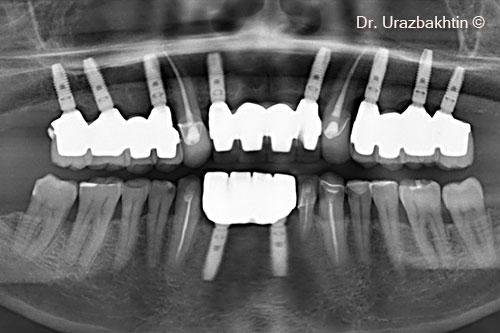

Final x-ray after 8 years